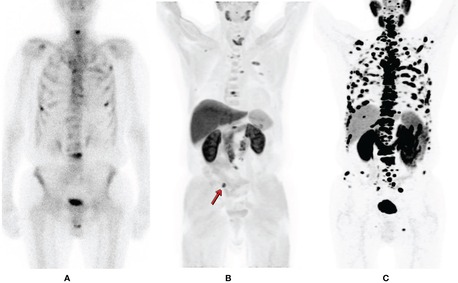

For men managing prostate cancer — whether newly diagnosed, post-treatment, or facing a rising PSA with no visible lesion on conventional imaging — a PSMA PET CT scan is now the most sensitive and clinically validated imaging tool available. Using Gallium-68 labeled PSMA tracer, this scan binds specifically to prostate-specific membrane antigen on cancer cells, lighting up even microscopic metastatic deposits that standard CT or bone scans routinely miss. Recent global trials confirm PSMA PET CT allows nearly half of men to avoid unnecessary biopsies entirely. Picture This in Mumbai generates its own 68Ga-labeled PSMA molecules in-house using a dedicated Gallium generator — a capability that sets them apart from most centres. Expert reporting is provided by Dr. Bhavin Jankharia and Dr. Nusrat Shaikh, with same-day results available for morning studies. Whether you need initial staging, biochemical recurrence evaluation, or treatment response monitoring, this is where precision prostate cancer imaging happens in Mumbai. Don't let uncertainty stall your care — contact Picture This now and get the diagnostic clarity your oncologist needs.